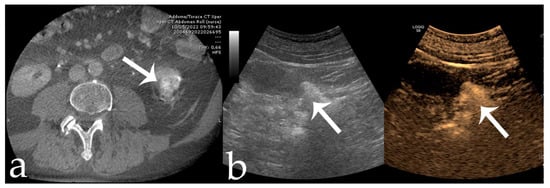

Figure 3. 80 yr old male with intra-cortical RCC of the left kidney lower pole (15 × 15 mm) (arrows): (a,b) pre-operative CECT and US; (c) pre-embolization angiographic study; (d,e) post-embolization control after 18-Onyx and indocyanine mixture administration.

Figure 4. Same case as Figure 3. (a,b) Post-procedural CBCT and CEUS showing complete tumor devascularization (arrows).